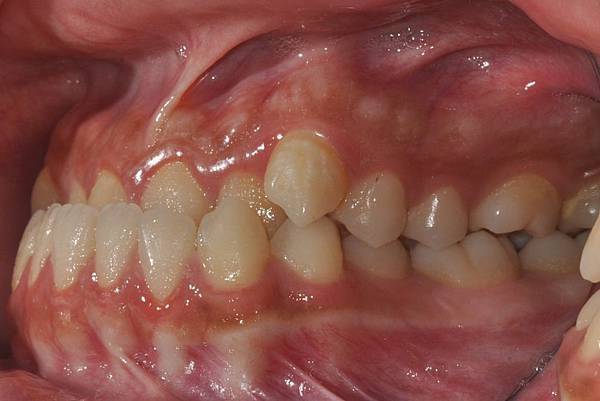

戽斗下唇突出改善案例

本案例因為考量到患者下唇突出

便建議拔除上下四顆小臼齒將

下唇內收

也改善了

前牙錯咬

的問題~

治療前/治療後

-以上案例由林昇進醫師提供